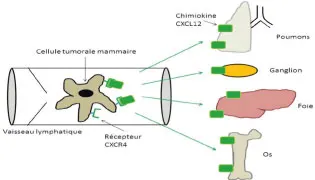

Rôle des chimiokines

Les chimiokines sont des petits polypeptides qui contrôlent l’adhésion et la migration des cellules du système immunitaire porteuses de certains récepteurs membranaires. L’interaction entre les chimiokines et ces récepteurs membranaires engendre une migration cellulaire directionnelle. L’expression de certaines chimiokines spécifiques a été retrouvée de manière plus importante dans certains organes qui sont le siège préférentiel des métastases. Ainsi, la présence de ces chimiokines dans ces organes va promouvoir la migration et l’adhésion de cellules tumorales exprimant le récepteur correspondant à la chimiokine.

Dans la dissémination métastatique du cancer du sein, l’interaction serait exclusive entre CXCL12, qui est la chimiokine qui joue un rôle important, et CXCR4, son récepteur correspondant Absent du tissu mammaire sain, ce récepteur membranaire est surexprimé dans le cancer du sein, avec un mécanisme qui reste mal défini [20]. De fortes concentrations de CXCL12 sont retrouvées au niveau des ganglions lymphatiques, induisant un gradient de concentration dans les vaisseaux lymphatiques. Ce gradient de concentration entraîne une attraction des cellules tumorales porteuses du récepteur CXCR4, favorisant ainsi le développement de métastases au niveau des ganglions [21]. En outre, d’autres données suggèrent que CXCL12 joue un rôle dans la dissémination de métastases dans des organes plus éloignés, car des concentrations élevées ont été retrouvées également au niveau pulmonaire, hépatique, osseux et cérébral, qui sont aussi des sites métastatiques préférentiels du cancer du sein [22, 23] (figure 25.1).

Fig25.1-2

Le système lymphatique et la lymphangiogenèse sont impliqués dans la dissémination métastatique du cancer. Cette implication passe par l’intermédiaire de l’intravasation des cellules tumorales dans les canaux lymphatiques permise par la sécrétion de facteurs de croissance ou de chimiokines au sein du système lymphatique. Les mécanismes qui gouvernent le passage de cellule tumorales au sein des vaisseaux lymphatiques, de même que ceux qui permettent la colonisation de tissus à distance demandent encore à être précisés, mais ils pourraient fournir des cibles pou le développement de stratégies thérapeutiques permettant de s’opposer à la dissémination métastatique.